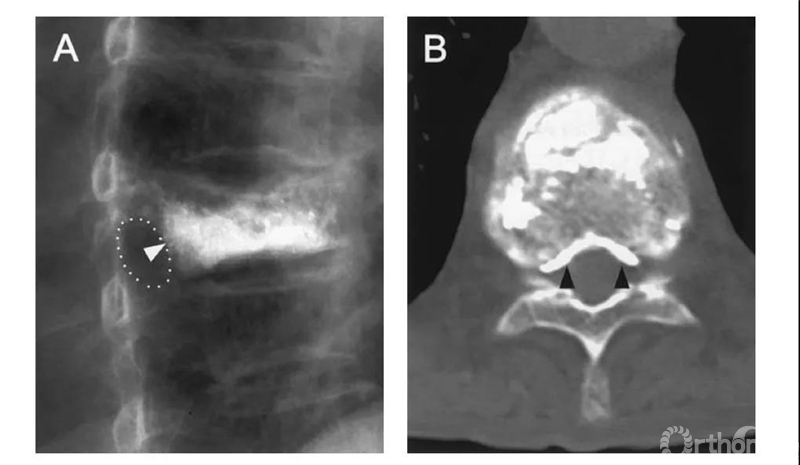

比如这例,侧位X片看骨水泥在椎弓根里,可CT一扫发现已经渗漏进入椎管。

侧位X片看骨水泥在椎体里,CT显示渗漏进入椎管。

侧位X片看骨水泥在椎间孔周缘,CT显示渗漏进入椎管,累及椎间孔。